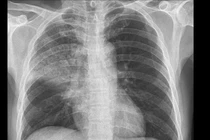

Bệnh nhân Đ.Đ.Th., 46 tuổi, xơ gan do rượu, nhiều lần xuất huyết tiêu hóa do giãn tĩnh mạch thực quản và phình vị. Trước đó, anh từng được nội soi thắt vòng cao-su và nút tắc búi giãn xuyên gan (ATO). Lần này, bệnh nhân nhập viện trong tình trạng xuất huyết tiêu hóa tái phát, cổ chướng nhiều, phù hai chi dưới và đau tức vùng bụng.

Sau hội chẩn liên chuyên khoa Nội Tiêu hóa, Ngoại Tổng hợp và Điện quang can thiệp, bệnh nhân được chỉ định thực hiện can thiệp TIPS. Đây là thủ thuật được Bộ Y tế xếp loại phẫu thuật loại I, đòi hỏi trình độ kỹ thuật và trang thiết bị cao.

Sau khi stent được đặt thành công, dòng lưu thông giữa tĩnh mạch cửa và tĩnh mạch chủ được tái lập, áp lực tĩnh mạch cửa giảm rõ rệt. Bệnh nhân tỉnh táo, sức khỏe ổn định và đang được theo dõi tại Khoa Hồi sức tích cực.